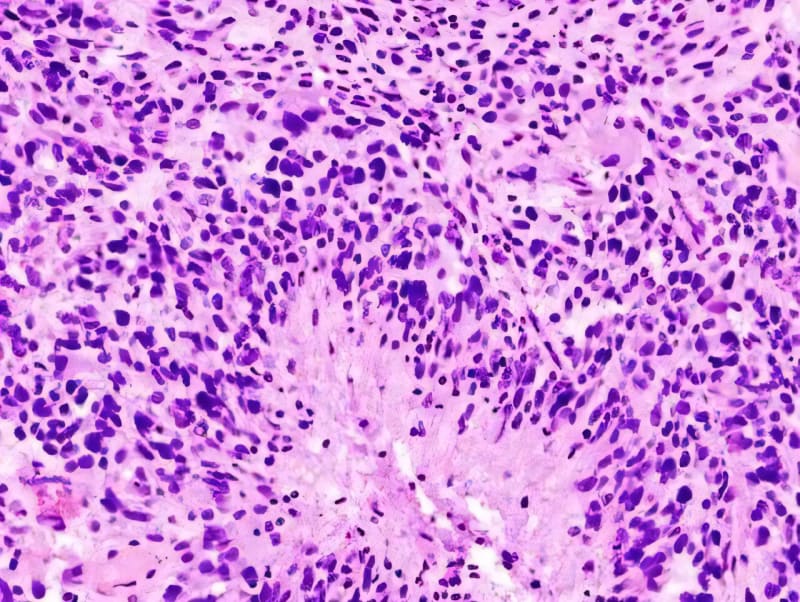

A 15-year study reveals that 42% of advanced follicular lymphoma patients can now be considered cured after standard treatment, challenging decades of medical belief that this cancer was incurable. Relapse rates dropped from nearly 7% in the first five years to just 0.6% after 15 years.